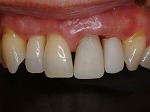

歯をより白く綺麗にしたいと思う方々は多いと思います。審美歯科とは、白い歯が見える口元だけではなく、機能的で歯周組織と顔貌に調和した自然美を追求する治療です。治療は短期間(歯冠修復・ホワイトニングなど)で終わるものから長期に渡る全顎的な治療(歯周病治療・矯正治療・インプラント治療など伴うケース)を行う症例もあります。当院での歯冠修復は

- ジルコニアクラウン修復

- メタルボンドクラウン修復

- グラスセラミッククラウン修復

- ハイブリットインレー、アンレー修復

- コンポジットレジン充填

等の歯冠修復を行っています。

◆ジルコニアクラウン修復

→

◆メタルボンドクラウン修復

◆オールセラミック修復